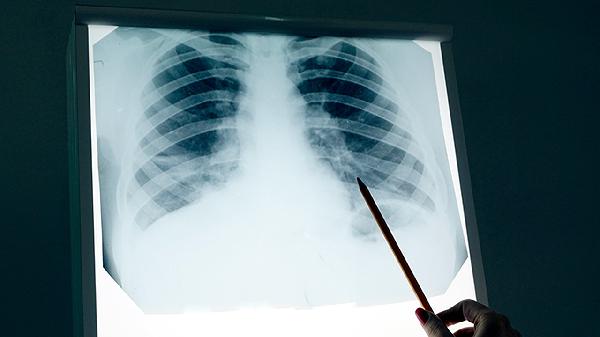

肺癌患者若选择中药辅助治疗,应前往正规中医院肿瘤科就诊,避免使用成分不明的偏方。治疗期间需定期复查影像学及肿瘤标志物,监测病情变化。保持均衡饮食,适量补充优质蛋白与维生素,避免辛辣刺激食物。根据体能状况进行散步、太极拳等低强度运动,维持心肺功能。家属需关注患者情绪变化,及时疏导焦虑抑郁心理,必要时寻求专业心理支持。